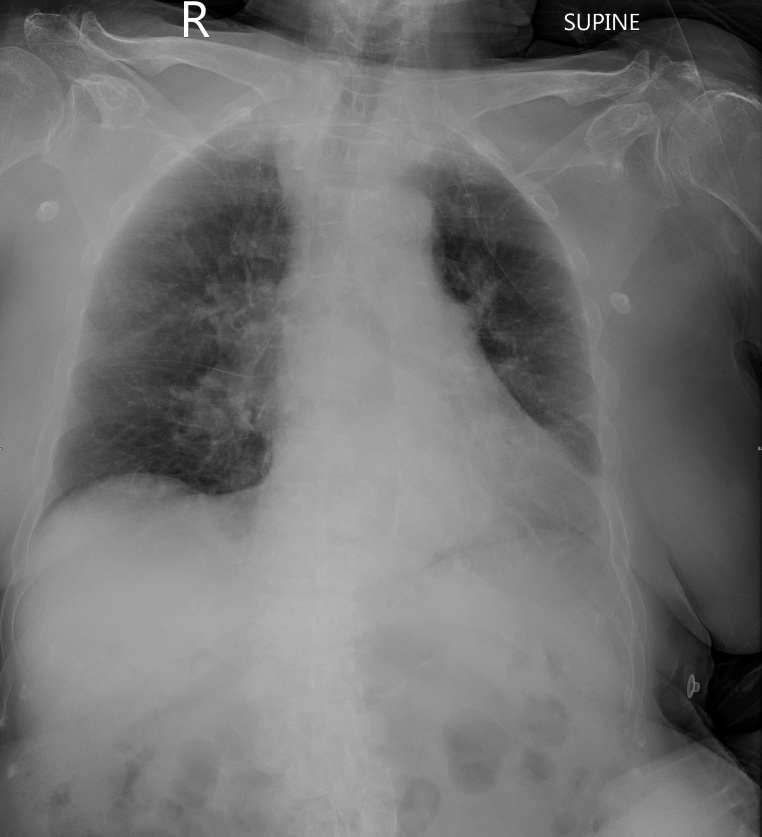

An 84-year-old woman with hypertension, CKD, diabetes, and Cushing syndrome presented with altered consciousness and dyspnea. On arrival, her vital signs showed BP 112/78 mmHg, HR 125 bpm, and SpO₂ 66% on room air. Physical examination revealed bilateral rales, and distant heart sounds. Chest X-ray revealed bilateral pulmonary congestion, cephalization of vessels, and no consolidation, suggesting heart failure.

Her ECG demonstrated ST depressions and T wave inversions in leads V2-V6, I, II, aVL, and aVF, indicating myocardial ischemia, potentially secondary to hypoxia and coronary artery disease. Laboratory results showed elevated Troponin I at 1.55 ng/mL and NT-proBNP at 7310 pg/mL, consistent with acute decompensated heart failure.